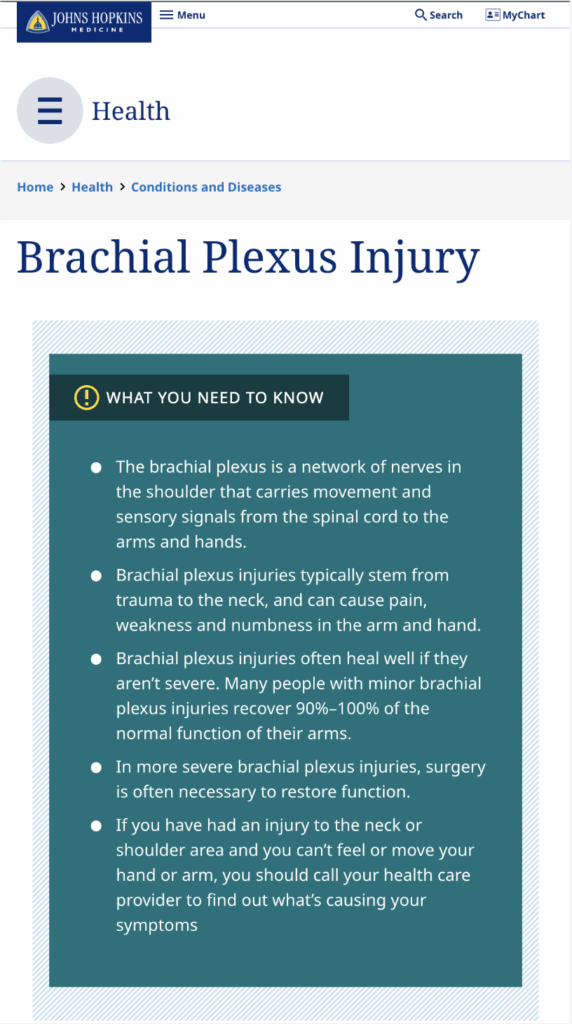

- Brachial plexus injury

- Erb’s palsy